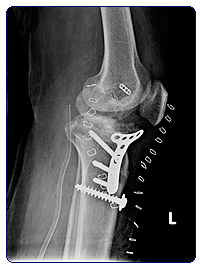

Case 2: This young man sustained a fracture of upper part of leg bone in a traffic accident. The fracture was in multiple places. There was also a big wound on the front of the knee. There was underlying rupture of one of the important tendons of the knee - the patellar tendon. The wound was badly soiled with roadside dirt.

The complexity of this case was that it had all the chances of possible complications such as infection, loss of knee strength due to injured main knee tendon, deformity and non union of the fracture itself, and finally, stiffness of the knee. On top of all this he happens to be an active young person. Such cases need carefully planned approach with multiple operations and involvement of the plastic surgery team. After 5 operations over a period of 6 months, this young man could finally walk on his legs with only a little limp.

Complex fracture just below the knee with big wound

After fixation, and skin healing